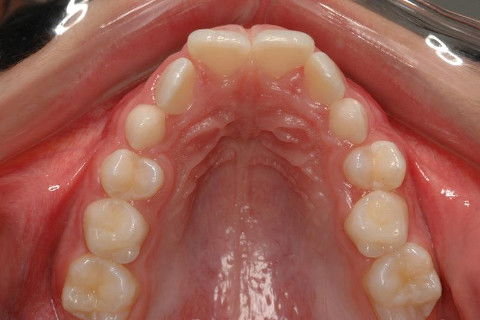

OCLUSAL SUP. FINAL

PACIENTE CLASSE II.

ATRESIA DE MAXILA.

SOBREMORDIDA.

CORREÇÃO: USO DO HAAS MULTIFUNÇÃO + AEB TRAÇÃO BAIXA.

APARELHO FIXO METÁLICO ROTH + ELÁSTICO DE CLASSE II.